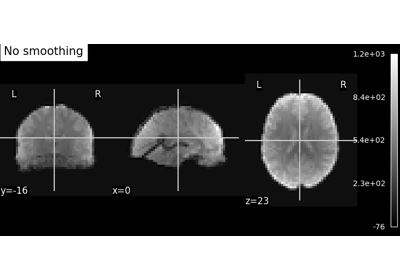

Smoothing an image